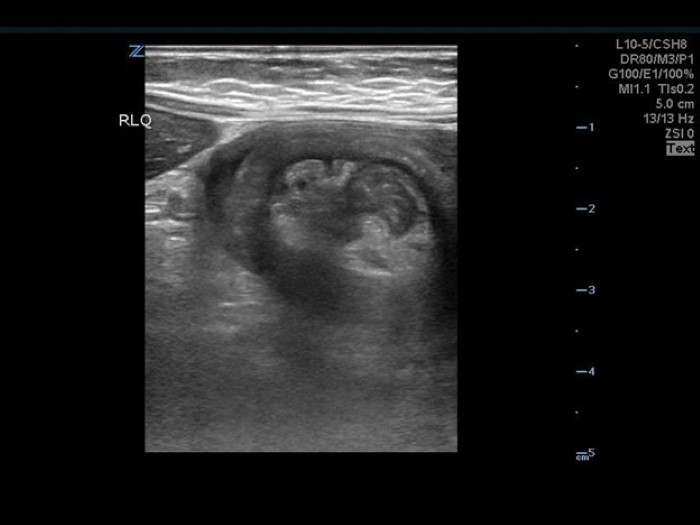

The linear probe is placed in the RLQ in the transverse position with indicator to the patient’s right. Identify the psoas muscle and iliac vessels lying medial. Once these structures are visualized, slide lateral and look superficially to identify the cecum. (Figures 1a,1b 1) Use graded compression-progressive increase and decrease of pressure to move any gas out of view. Keeping the lateral edge of the abdominal cavity in view (Figure 2), the ultrasound probe should slide cranial in traverse plane, visualizing the ascending colon until the hepatic flexure.  In this location, the colon turns just medial to the liver with the kidney deep in the view. (Figure 3) This is the most common location to identify ileocolic intussusception. If no tissue mass is identified, the probe should be turned to the sagittal plane with indicator toward the head (to keep the colon visualized in the transverse view) and moved across the transverse colon continuing to use graded compression to look for a tissue mass consistent with intussusception. Once at the splenic flexure (Figure 4), the probe should be transitioned back to the transverse orientation to interrogate the descending colon.

The abnormal structure of intussusception is a rounded tissue mass in the transverse axis with a hyperechoic center and hypoechoic outer muscle layer (Figure 5) and in long axis appears as a “pseudokidney.” (Figure 6) Outer dark edge to edge should be at least 2cm.1-3 Smaller structures with similar appearance are likely ileo-ileal intussusception, which is usually psychologic and does not typically require intervention.

10-2024 Article7-5.jpgFigure 5. Short axis view of intussusception. Note the hyperechoic center and the hypoechoic outer layer, and the liver lying lateral.

10-2024 Article7-6.pngFigure 6. Long axis Intussusception, sometimes referred to as the “Pseudokidney” as it mimics the kidney’s shape in sagittal.